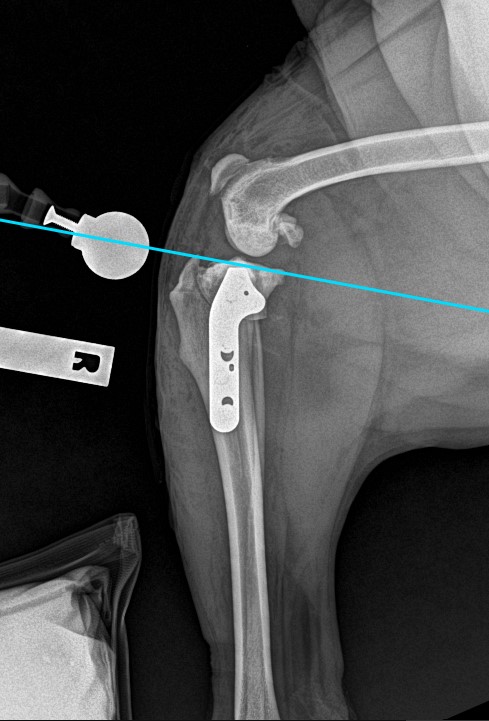

TPLO Post Op